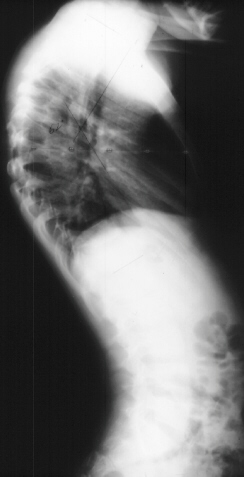

Coinciding with current literature recommendations for treatment of severe dysplastic kyphoscoliosis, the patient underwent an Anterior-Posterior spinal fusion from T1-T10. The scoliosis was corrected to 21 degrees and kyphosis to 34 degrees. The procedure was augmented with a rib strut graft and was tolerated well. No neurologic complications occurred and the patient developed a solid fusion by one year without progression of the curvature. He is currently 5 years post-op playing in sports and without pain.

Considered pathologic if greater than 49 degrees. Possibly secondary to collapse of apical dystrophic vertebrae with flexion force created by rotation with the scoliosis. Kyphosis contributes more to paraplegia as a result of tension on cord with flexion. This typically occurs in the upper thoracic region where the cord -canal ratio is most critical.